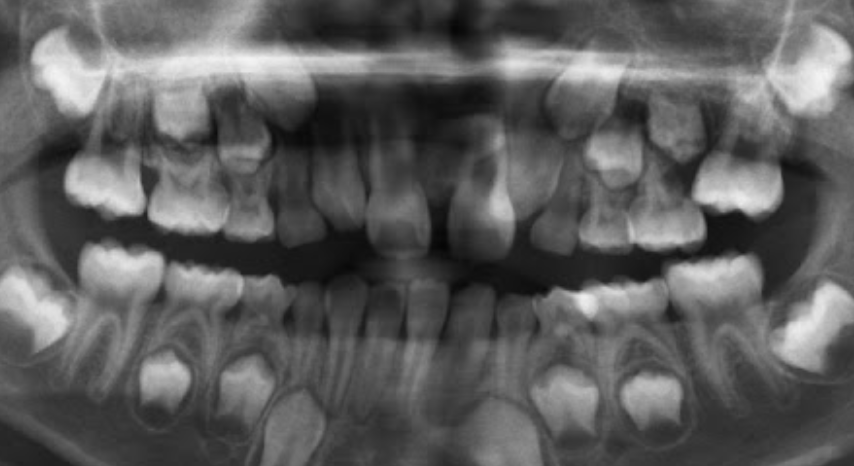

1.Lower adult CI there? YES. so def 6-7

1. Upper adult CI there (they normally erupt 7-8)? NO, baby ones should shed at 6-7.

Conc: pt. Is 6 y.o